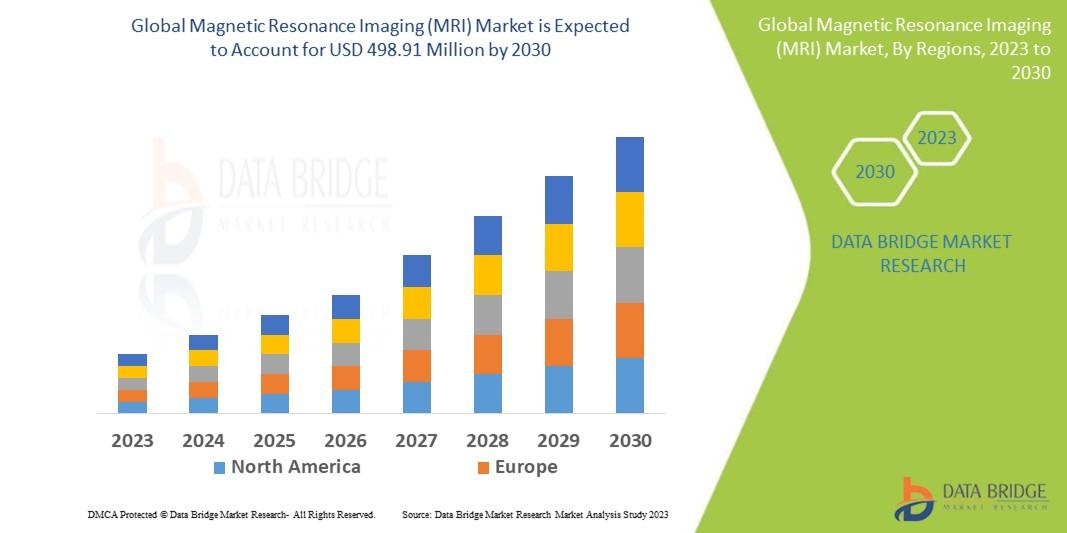

Magnetic Resonance Imaging (MRI) Market Growth, Demand and Forecast 2030

The global Magnetic Resonance Imaging (MRI) Market is expected to experience substantial growth between 2024 and 2030. Starting from a steady growth rate in 2023, the market is anticipated to accelerate due to increasing strategic initiatives by key market players throughout the forecast period.

North America, particularly the United States, will continue to exert significant influence that cannot be overlooked. Any shifts in the United States could impact the development trajectory of the Magnetic Resonance Imaging (MRI) Market. The North American market is poised for substantial growth over the forecast period. The region benefits from widespread adoption of advanced technologies and the presence of major industry players, creating abundant growth opportunities.

Similarly, Europe plays a crucial role in the global Magnetic Resonance Imaging (MRI) Market, expected to exhibit impressive growth in CAGR from 2024 to 2030.